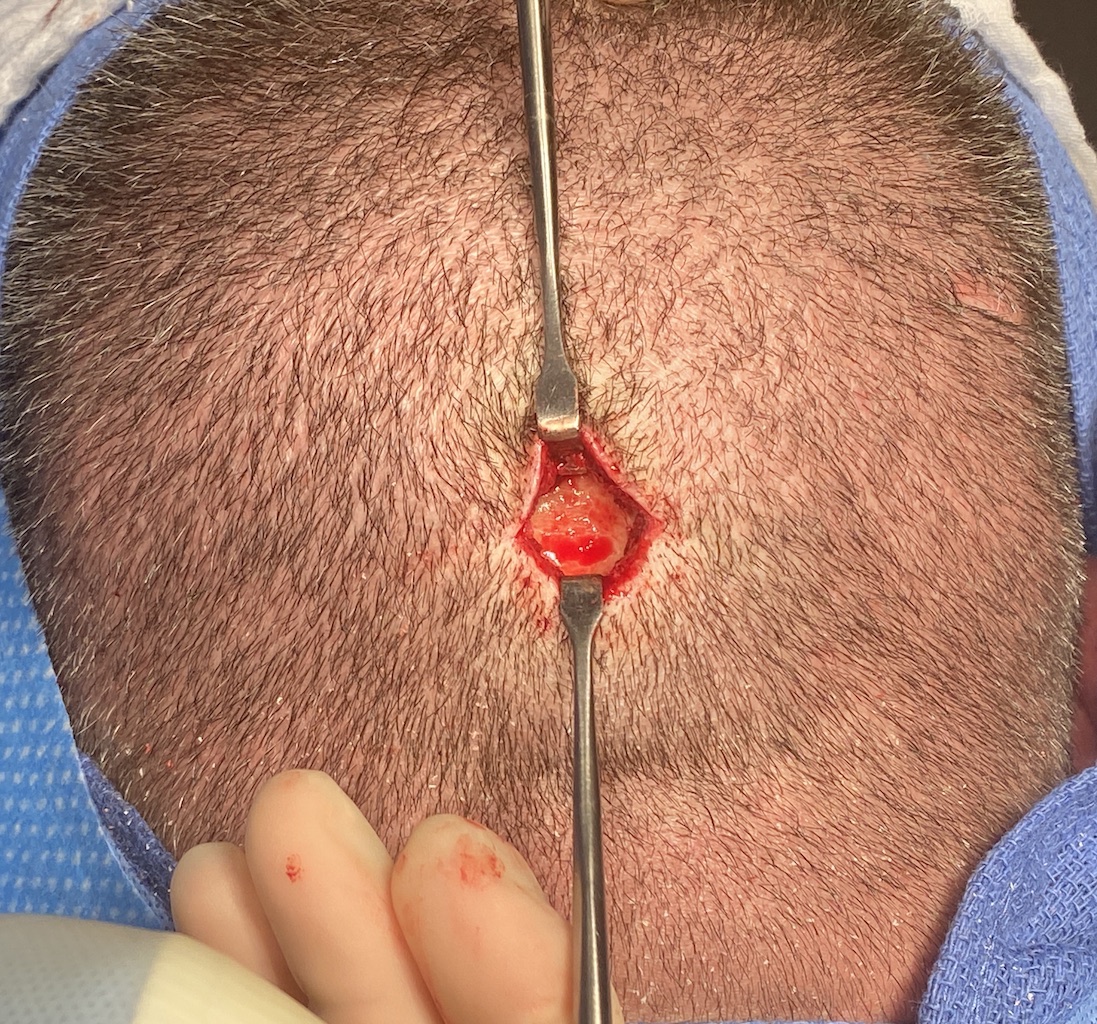

Desire for reduction of prominent occipital knob deformity.

Intraoperative result from occipital knob skull reduction through a direct small scalp incision.

Desire for reduction of prominent occipital knob deformity.

Intraoperative result from occipital knob skull reduction through a direct small scalp incision.